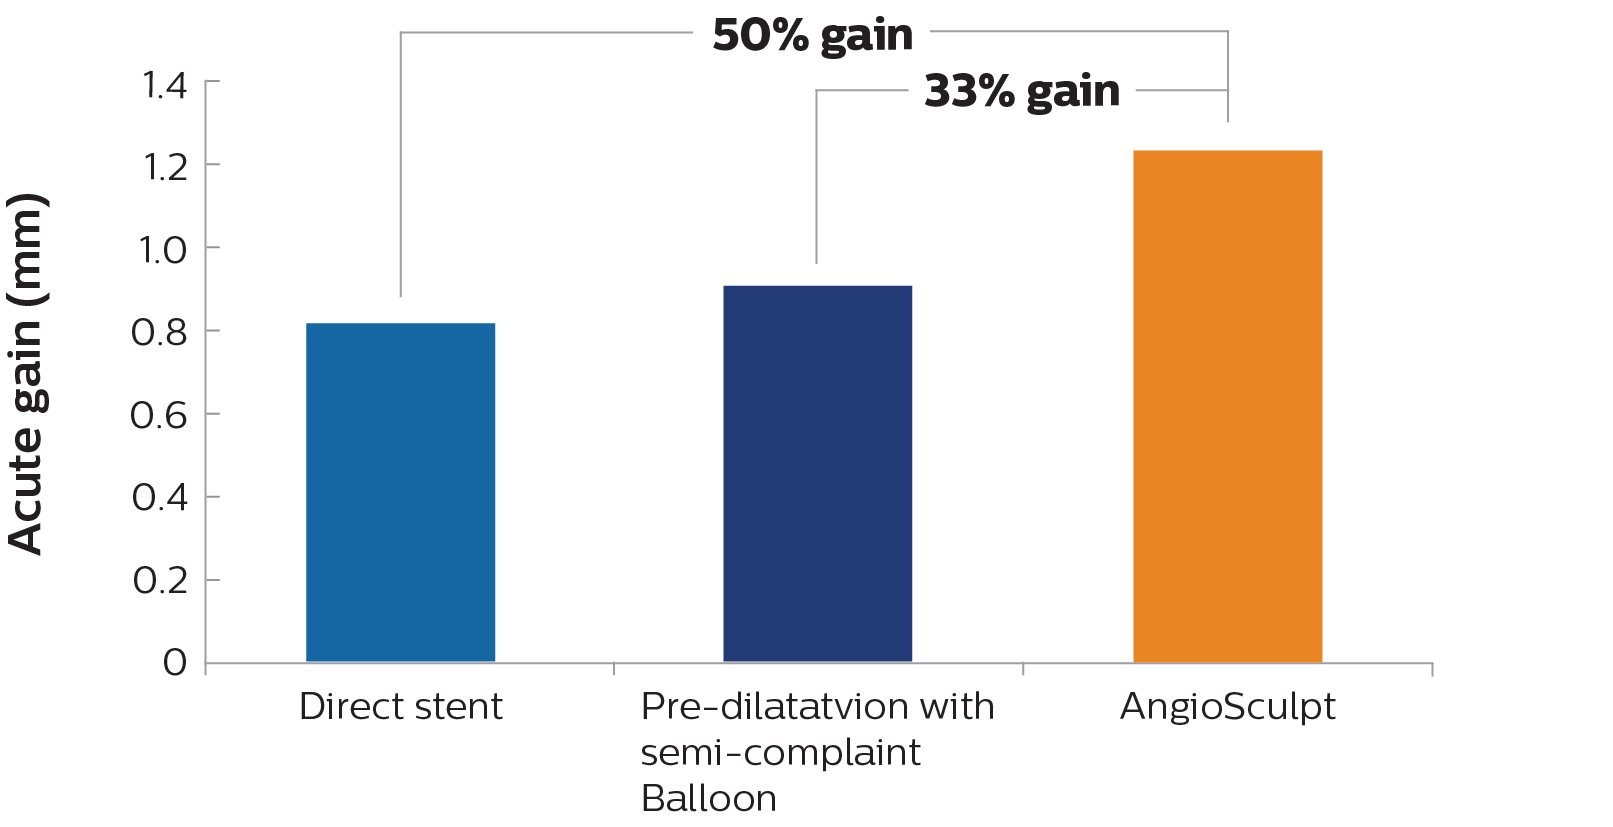

IVUS-guided vs. angiography-guided outcomes3

1. Xu B., Gao R. L., Zhang R. Y., et al. Efficacy and safety of FIREHAWK abluminal groove filled biodegradable polymer sirolimus-eluting stents for the treatment of long coronary lesions: nine-month angiographic and one-year clinical results from TARGET I trial long cohort. Chinese Medical Journal. 2013;126(6):1026–1032. 2. Ahn J. M., Park D. W., Kim Y. H., et al. Comparison of resolute zotarolimus-eluting stents and sirolimus-eluting stents in patients with de novo long coronary artery lesions a randomized LONG-DES IV trial. Circulation: Cardiovascular Interventions. 2012;5(5):633–640. 3. Costa JR, Mintz GS, Carlier SG, et al. Nonrandomized comparison of coronary stenting under intravascular ultrasound guidance of direct stenting without predilation versus conventional predilation with a semi-compliant balloon versus predilation with a new scoring balloon. Am J Cardiol. 2007;100:812-817. 4. Hong S-J, et al. “Effect of Intravascular Ultrasound-guided Drug-Eluting Stent Implantation: Five-Year Follow-Up of the IVUS-XPL Randomized Trial, JACC: Cardiovascular Interventions (2020), doi: www.doi.org/10.1016/j.jcin.2019.09.033.